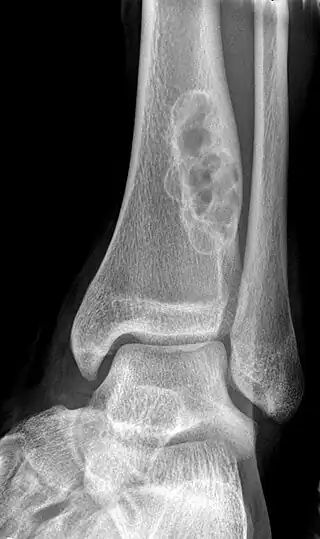

A bone tumor may be felt on examination, following which a plain X-ray is usually carried out.[4][13] Imaging is interpreted with the location of the lesion and the person's age being taken into account.[14]

X-ray appearances of different types of bone tumors in < 30 years. -

X-ray appearances of different types of bone tumors in > 30 years. -